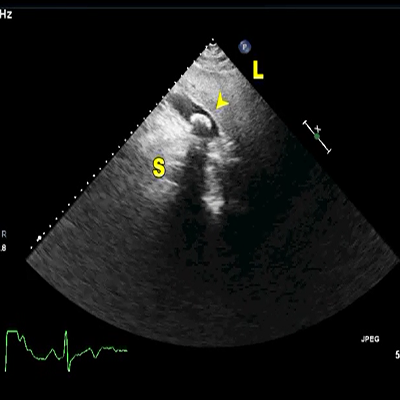

LVO-RA shunt (S) just beneath the TV